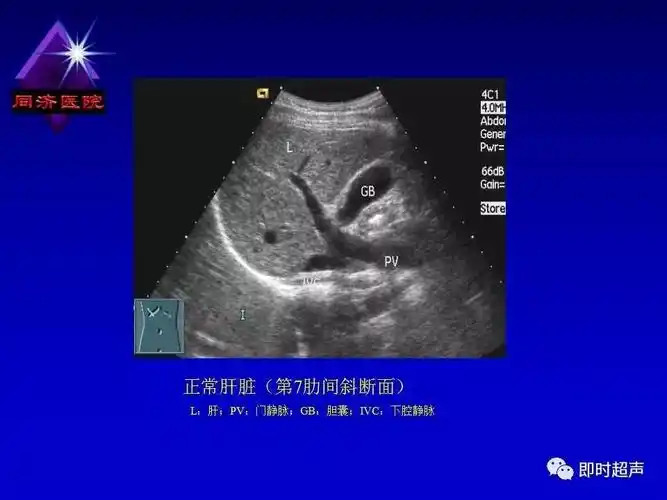

正常肝脏的超声解剖及局限病变的超声诊断